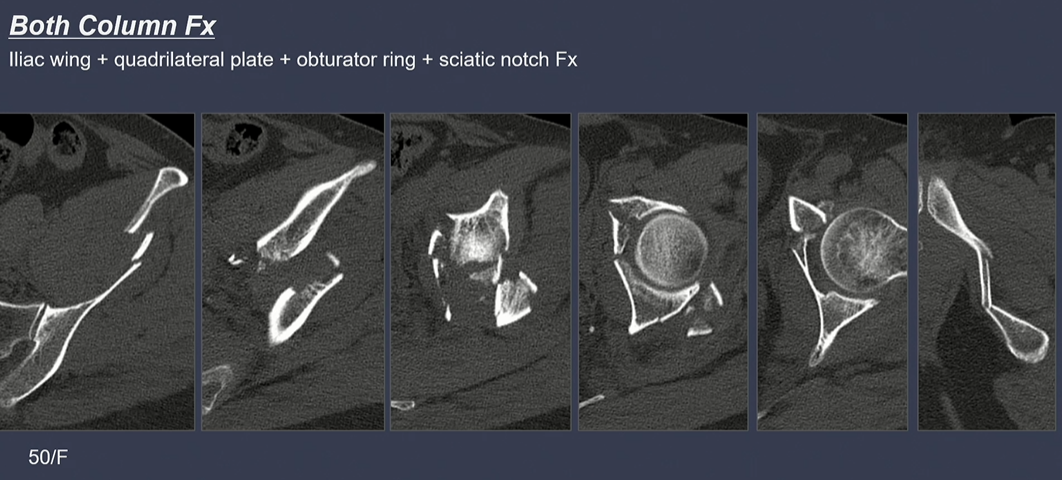

CT상 골절선 확인. 가장 좌측 iliac wing, 중간 사진은 Quadrilateral plate에 골절선이 있음.

iliac wing쪽 골절선(녹색 점선)에 더해서, sciatic notch로 이어지는 골절선(녹색 화살표)을 확인.

Spur sign은 both column fracture의 pathognomonic sign.